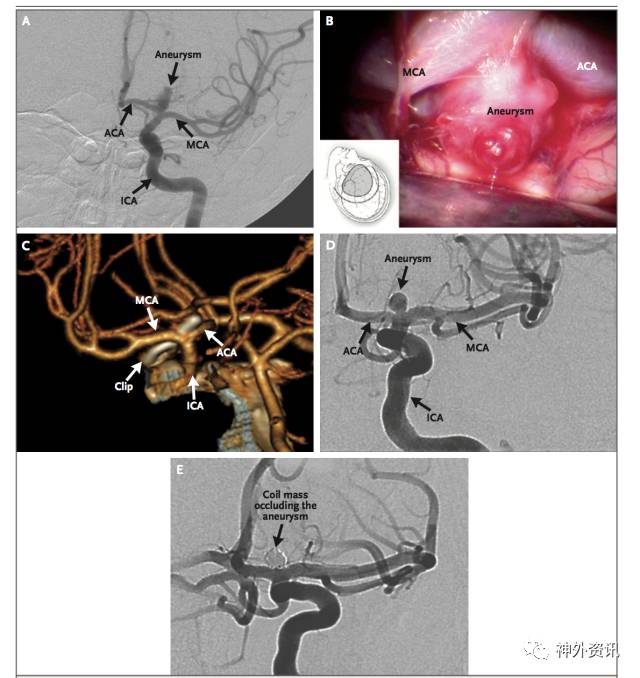

动脉瘤破裂后的初期治疗是指诊断明确之前需紧急防止危及生命的并发症,包括建立安全气道,稳定心血管功能和控制癫痫发作等。SAH分级系统最常用的两种是Hunt-Hess分级和WFNS分级,两种分级系统都重点评估脑损伤的严重程度。头颅CT平扫是诊断SAH首要检查手段(图2);起病后的前三天,CT扫描的灵敏度接近100%,但在5-7天后,其灵敏度下降到50%。头颅CT扫描还能显示血肿占位和急性脑积水。如果临床高度怀疑SAH,但CT扫描阴性,有必要作腰穿化验脑脊液。CTA可以检测到2mm大小的动脉瘤,但可能漏诊血泡状动脉瘤或因血栓形成的动脉瘤。DSA是诊断动脉瘤和指导治疗的金标准;三维血管重建结合二维血管重建有利于评估动脉瘤和选择治疗方案(图3)。药物干预可以降低动脉瘤再出血的风险;动脉瘤再破裂可进一步增加死亡率和加重神经功能障碍。SAH最初的24小时,动脉瘤再破裂风险为4%-14%。高血压提升动脉瘤再破裂的危险,但目标血压范围需进一步论证。抗纤维蛋白溶纤治疗可以稳定出血部位血栓,抗纤溶治疗的患者动脉瘤再破裂率为2%,而未抗纤溶治疗患者动脉瘤再破裂率为11%。但抗纤溶治疗并不能提高患者总体预后,而且可能增加深静脉血栓形成和迟发性脑缺血的发病率。20%的SAH患者出现癫痫发作,从而引起血流动力学不稳增加动脉瘤破裂再出血率;然而当前并没有RCT证据支持抗癫痫治疗和推荐常规药物预防癫痫。对于破裂动脉瘤实施开颅手术夹闭或介入栓塞的治疗是安全有效的;应推荐患者到手术量大的脑血管病中心和请经验丰富的专业医生救治。ISAT和BRAT两项RCT研究比较介入栓塞治疗和开颅手术夹闭的预后发现,手术夹闭动脉瘤的闭塞率高和复发率低,但术后1年随访发现,介入栓塞治疗的患者功能恢复更良好。对于颅内压增高或血肿压迫引起的局灶性神经功能缺损以及动脉瘤介入治疗困难时,需要作血管搭桥重建结合开颅夹闭动脉瘤治疗;对年龄小于40岁、神经功能良好的前循环动脉瘤患者,优先考虑开颅夹闭治疗。

图3. 血管造影示颈内动脉瘤治疗前后的影像。